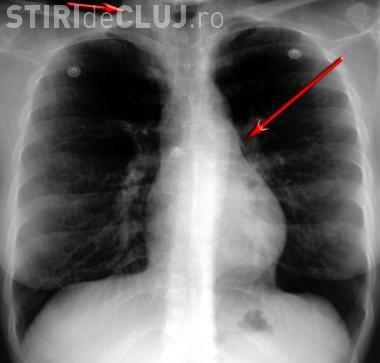

Băiețelul a fost adus din Baia Mare și a fost resuscitat fiind în stare foarte gravă. Cornel Aldea, managerul Spitalului de Copii Cluj, a declarat că băiețelul a înghițit sâmburi de migdale, ”pe care i-a aspirat și i-au ajuns în plămâni”.

Pentru că se sufoca, medicii au fost nevoiți să îi facă o intervenție deosebit de riscantă, i-au aspirat plămânii. Astfel au fost scoși câțiva sâmburi de migdale, pe care copilul i-a introdus în gură și i-a înghițit.